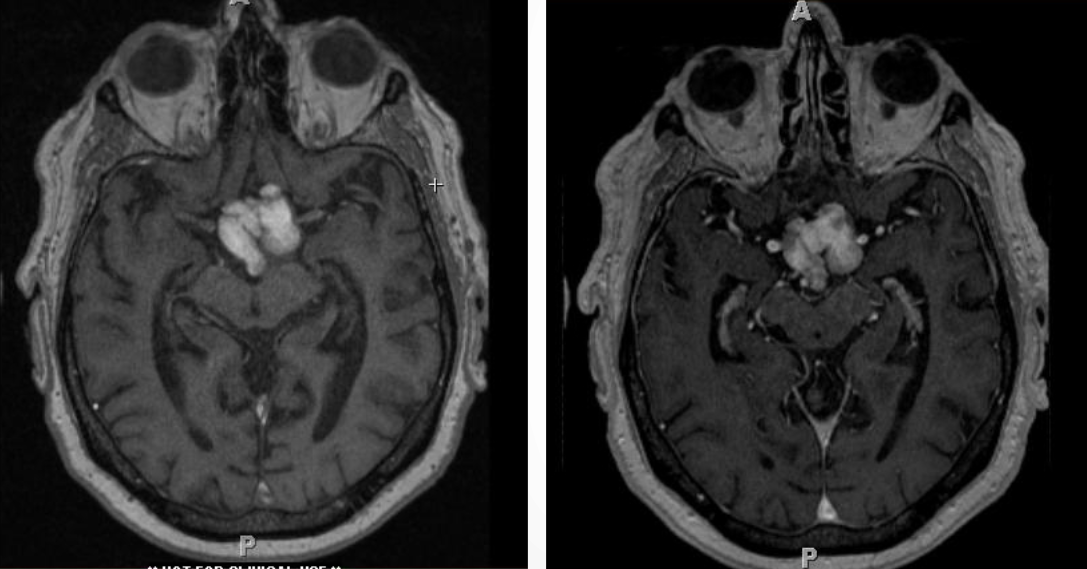

Радиологическая визуализация

Магнитно-резонансная томография (МРТ) превосходит компьютерную томографию (КТ) в оценке локализации и распространения опухоли при КФО.

Хотя КТ необходима для того, чтобы показать степень кальцификации и взаимосвязь опухоли с изменениями костной структуры в основании черепа, МРТ детально выявляет взаимосвязь опухоли с окружающими сосудисто-нервными структурами, вовлечение турецкого седла, желудочков и задней черепной ямки, соотношение между опухолью и перекрестом зрительных нервов, наличие кистозного компонента и гидроцефалии.

МР-ангиография может быть полезной для демонстрации взаимосвязи опухоли с окружающим сосудом и при планировании хирургического вмешательства